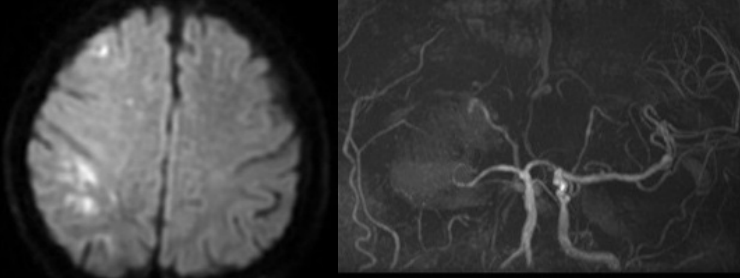

2021年11月2日,齐医附属一院卒中中心接诊一位55岁男性患者,就诊时已经意识不清,经过卒中中心夏海苗医生仔细检查后诊断为急性脑梗死,考虑大血管闭塞,立即启动卒中通道,磁共振证明为右侧颈内动脉闭塞。同时汇报王雷主治医师、王峰主任讨论,分析此患者静脉溶栓效果可能较差,最终决定给予血管内治疗。

术前影像检查